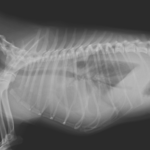

5歳の柴犬が最近、呼吸が早いとのことで主治医を受診しました。主治医のもとで胸水の抜去を行なったところ、乳び胸水の貯留が確認されました。精査と外科的な治療目的で紹介受診されました。CT検査および各種検査で乳び胸の原因となる腫瘍性疾患、寄生虫疾患、心臓疾患、外傷などは除外されました。十分な鎮痛処置を行なったのち右側開胸・開腹アプローチにより、結腸リンパ節からインドシアニングリーンにより胸管造影検査を行いました。造影により大動脈の背側に2本の胸管の走行が目視で確認されました。大動脈からこれを慎重に分離、チタンクリップで5箇所の結紮を行いました。さらに、横隔膜にウインドウを形成し、腹腔内から大網を牽引し、胸腔内で固定しました。さらに、慢性の乳び貯留による臓側の胸膜炎に伴い、著しく肥厚した心膜を横隔神経より腹側領域のを超音波メスにより切除を実施しました。この患者さんには胸管結紮、大網置換術、心膜切除術、これらの術式を組み合わせて手術を実施しました。トータルの手術時間はおよそ150分でした。術後5日に乳びの貯留が消失したため退院となりました。柴犬においてこの病気を経験する事が多いため、獣医師の仲間に尋ねると、どうも遺伝的な背景が関与しているようです。今回の手術で完治しなければ、デンバーシャントなどのインプラントの埋入を行う予定です。